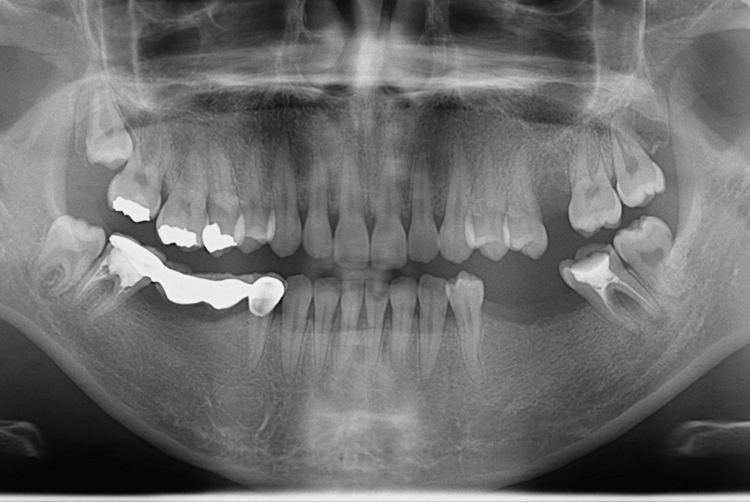

[임플란트] 어금니 임플란트

2012.3.30.jpg

세종치과는 많은 환자와 다양한 케이스를 바탕으로

항상 편안한 임플란트 수술을 제공하고자 노력하고,

오래동안 튼튼히 쓸 수 있는 임플란트 수술을 가장 큰 목표로 삼고 있습니다.